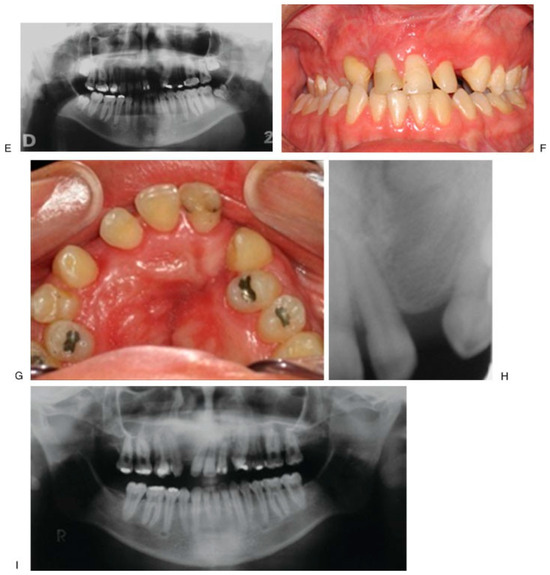

Figure 5. Initial aspect of the patient; fistula between 9–11 (A–E); alveolar bone transportation technique. Modified Hyrax device (VEGAX) (F–H); at 205 weeks of follow-up (I–K). - Case 4 was a 16-year-old male patient with cleft lip and palate sequel, treated with bifocal ABT (Figure 6).

Figure 6. Initial aspect (A–E); closing of alveolar fistula at 37 weeks of follow-up (F–I). - Case 5 was a 13-year-old female patient with dysmorphic syndrome, cleft lip and palate sequel, and active oronasal fistula, treated with trifocal ABT (Figure 7).